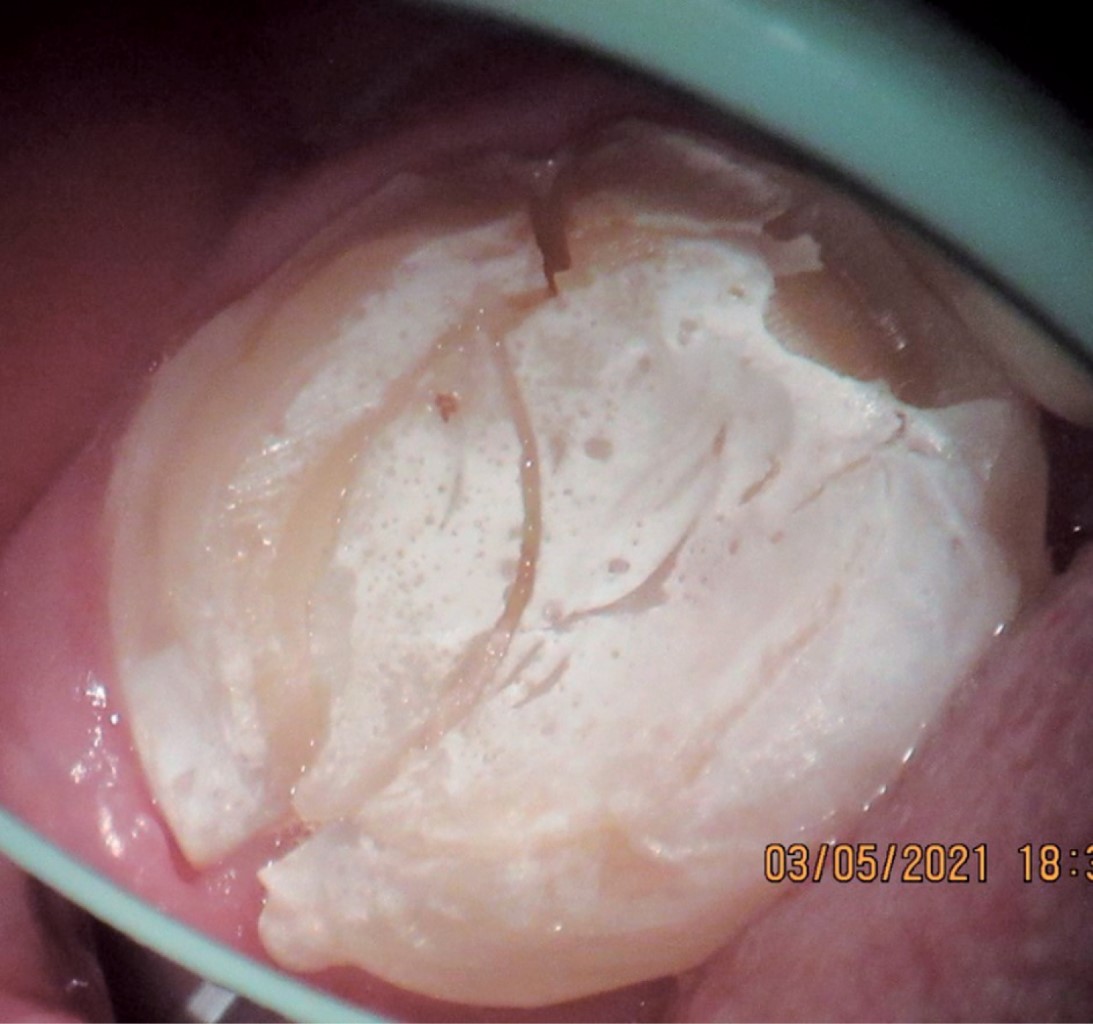

Se seleccionaron únicamente aquellos casos en los que se pudo obtener evidencia clínica, fotográfica y radiográfica de la presencia de por lo menos una fisura vertical o fractura dental que provocara síntomas y que ameritara la extracción del órgano dental por no ser tratable (Figuras 6, 7, 8, 9, 10, 11 y 12).

Se recolectaron en total 26 órganos dentales, los cuales fueron fotografiados con microscopio dental para comprobar la presencia de las fisuras y/o fracturas, en algunos casos se realizó una tinción con azul de metileno para mejorar la visión de las lesiones.

Se agruparon en una tabla por sexo, edad, diente afectado y fecha de presentación, además se estableció si se tenía o no un tratamiento endodóncico en órgano dental afectado y en caso de tener tratamiento endodóncico, se registró si se les había colocado endoposte; también se anotó si el órgano dental estaba restaurado y, de ser así, con qué material; se estableció la dirección de la fisura o fractura en los diferentes planos y, por último, se observó si el diente afectado tenía alguna lesión cariosa (Tabla 1).